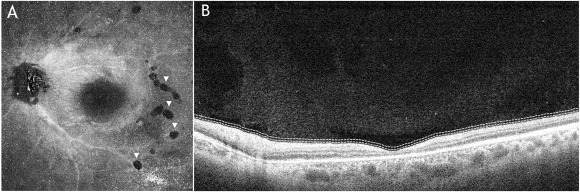

玻璃体Enface OCT显示玻璃体细胞的高反射点和颞侧及颞下方几个不透明的小腔隙,我们称之为“虫洞”(图4)。这些虫洞可能是线虫穿过玻璃体的地方。

图4:(A)左眼玻璃体Enface OCT,位于内界膜(ILM)上方约10μm处,高反射点提示玻璃体细胞,颞侧及颞下方小的低反射腔隙(箭头)提示先前蠕虫运动产生的虫洞;(B) 相应的B扫描图像。